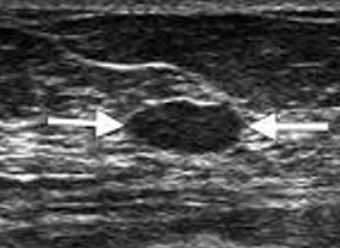

What is this?

A

US of breast. Dark mass could be a cyst.